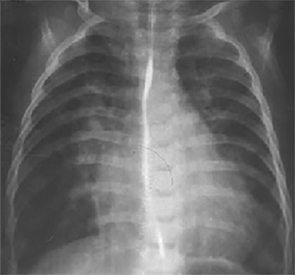

PA and Lateral

Click on the xrays to enlarge them.

Choose the best interpretation of the chest X rays:

RV enlargement, dilated

pulmonary trunk, increased pulmonary

arterial vascularity

LA/biventricular enlargement,increased pulmonary arterialvascularity

LV enlargement, aortic dilatation

RV hypertrophy, smallpulmonary trunk, decreasedpulmonary arterialvascularity

Dilated pulmonary trunk, normal vascularity